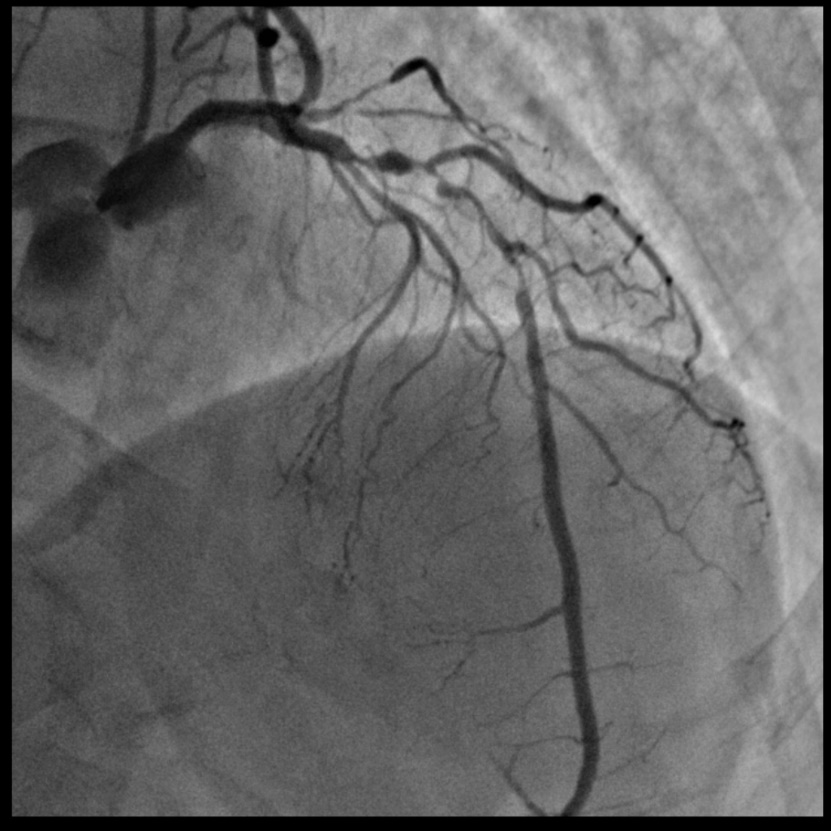

胡洵教授应用TRUEVISION® & VivoHeart®系统指导完成了一例前降支弥漫病变的PCI治疗。该名患者前降支病变长度超过60mm,传统IVUS导管回撤耗时超过1分钟,使用TRUEVISION® & VivoHeart®系统则仅用时7秒即完成了整个病变的评估。胡洵教授指出国产新型IVUS导管术中高速回撤的优秀表现,不仅给手术医生及患者节省了宝贵的手术时间,而且更为重要的是可以有效减少患者在IVUS检查过程中可能引发的心肌缺血风险。

术前